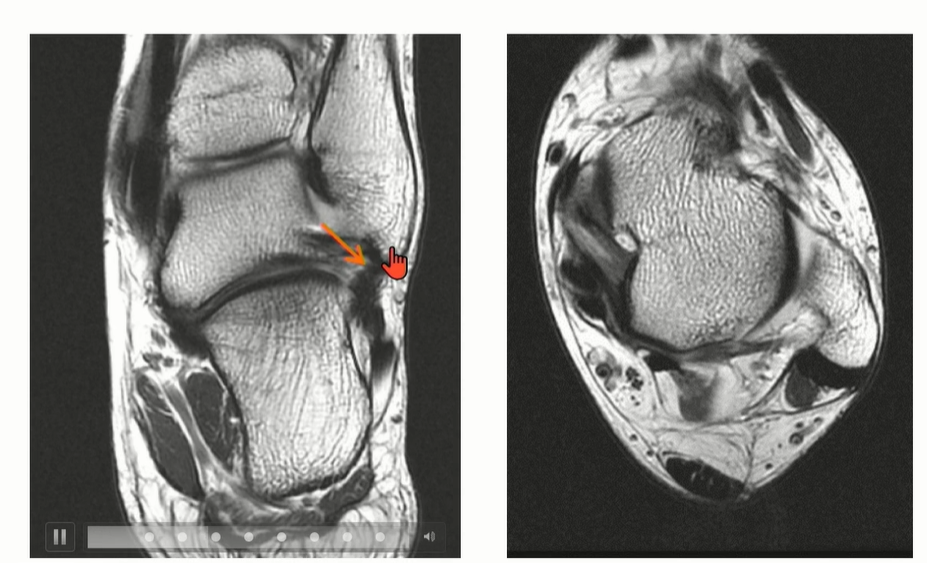

2-2 . CFL (Calcaneofibular ligament)

ATFL과 떨어져서 기시한다는 이야기도 있었지만, Just below ATFL로 이해하면 좋을 것 같다.

Peroneal tendon을 landmark로 이용해서 CFL를 찾는 것도 연습해야 함.

Axial cut과 coronal cut에서 모두 확인할 수 있는데, Axial cut의 경우에는 peroneal tendon 내부에 위치한 것을 확인할 수 있다.